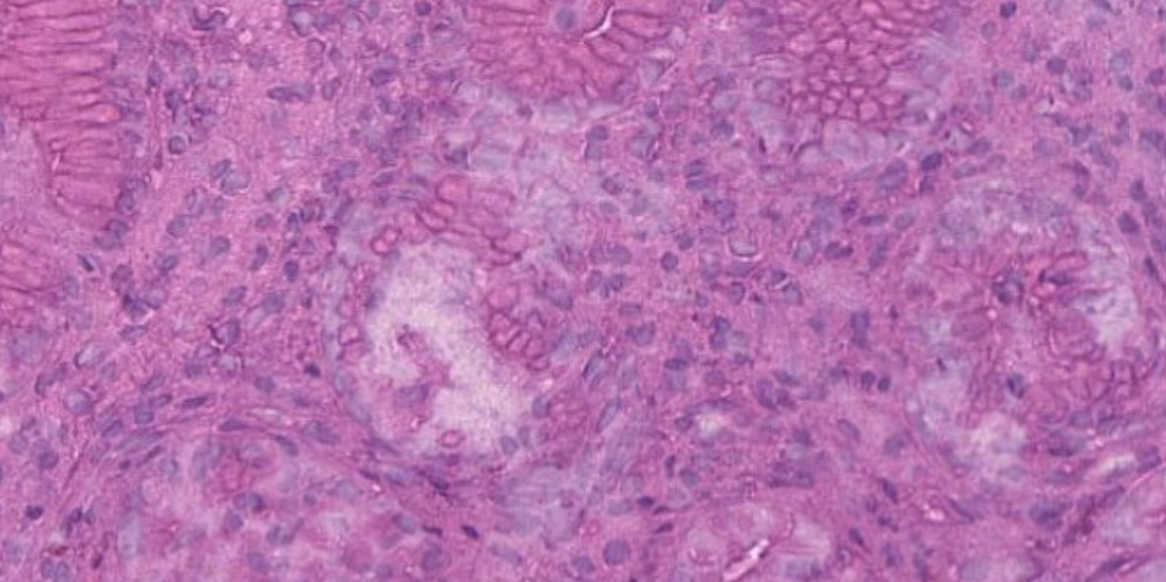

Страница гистолога: Плохая депарафинизация?

Сегодня мы поговорим об артефакте, с которым, наверное, многие сталкивались - это плохая депарафинизация срезов перед окрашиванием. 📍Как вы думаете, почему вообще может возникнуть такая проблема?

Сегодня мы поговорим об артефакте, с которым, наверное, многие сталкивались - это плохая депарафинизация срезов перед окрашиванием.

📍Как вы думаете, почему вообще может возникнуть такая проблема?